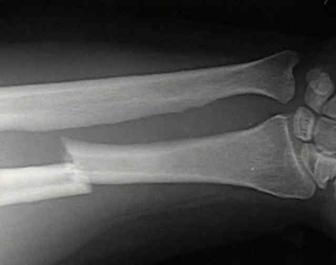

Fracturi simple: SPIRALA OBLICA TRANSVERSALA

Fractura spirala de Fractura transversa de diafiza femurala Fractura spirala de diafiza tibiala

diafiza humerala

Fractura spirala de diafiza tibiala Fractura oblica de diafiza tibiala Fractura transversala de diafiza tibiala